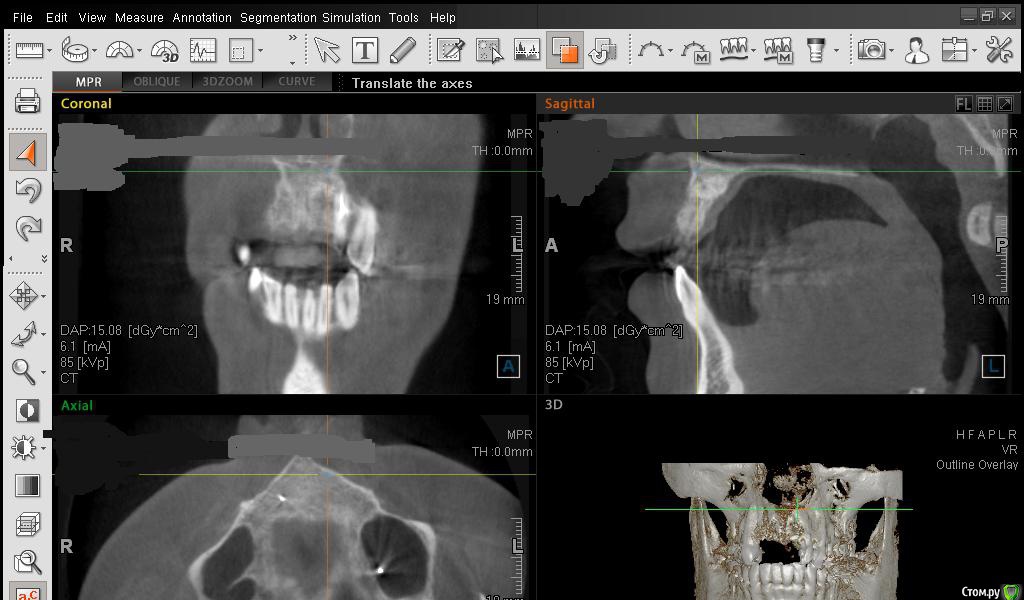

Сестричка Опубликовано 2 марта, 2015 Автор Поделиться Опубликовано 2 марта, 2015 Еще пара срезов Ссылка на комментарий

АнтонТЛТ Опубликовано 2 марта, 2015 Поделиться Опубликовано 2 марта, 2015 Сам крест еще нужно повернуть, чтобы было одна полоса креста была параллельна краю челюсти Ссылка на комментарий

Сестричка Опубликовано 3 марта, 2015 Автор Поделиться Опубликовано 3 марта, 2015 Ура! Ура! Ура! Сходила к докторам, теперь все конкретно и ясно стало! Кости наросло достаточно, костной пластики не потребуется. Но без пластики десны никак не обойтись и необходимого объема с одного тоолько неба будет недостаточно, так что пришлось согласиться на трансплантат, так как эстетически значимая зона и все должно быть красиво Вообщем теперь буду ждать саму имплантацию. Хирург молодец, даже свой ноутбук взял и там прямо стал в объеме импланты моделировать в моей челюсти Ссылка на комментарий